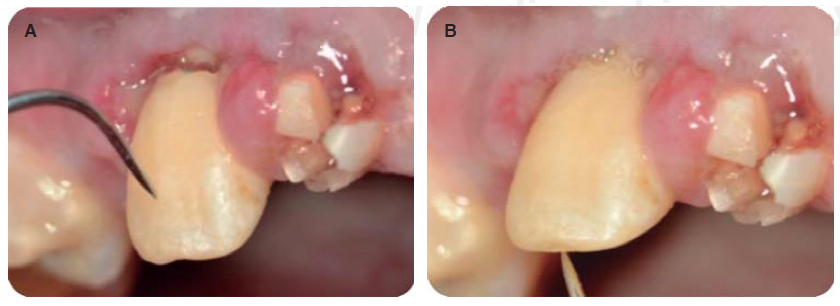

Alargamientos de coronas con fines endodónticos y restaurativos

Con una hoja de bisturí 15c, se realiza una incisión a bisel interno y luego una intrasurcal para eliminar un collar de encía y continuar levantando un colgajo de espesor total para exponer la estructura radicular remanente (Figura 8).

Se realizan las medidas con una sonda periodontal, para determinar la cantidad de tejido óseo que se debe eliminar con la osteotomía y osteoplastia para asegurar el efecto férula necesario para las restauraciones provisionales. Se mide con la sonda para asegurar una osteotomía de mínimo 3 mm (Figura 9), se procede a suturar con puntos simples (Figura 10).14